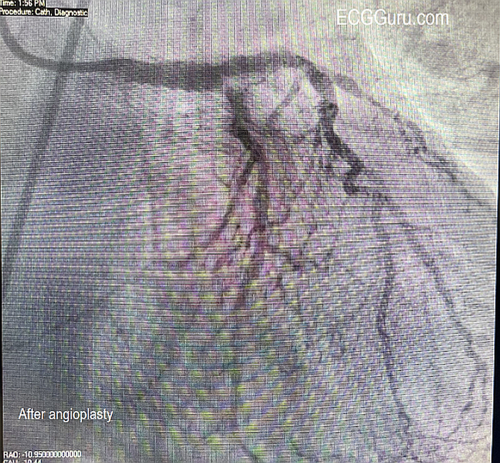

Followup:   The patient was taken to the cath lab and had angioplasty of an occlusive mid-LAD (left anterior descending) lesion and a partially-occlusive mid-RCA lesion.